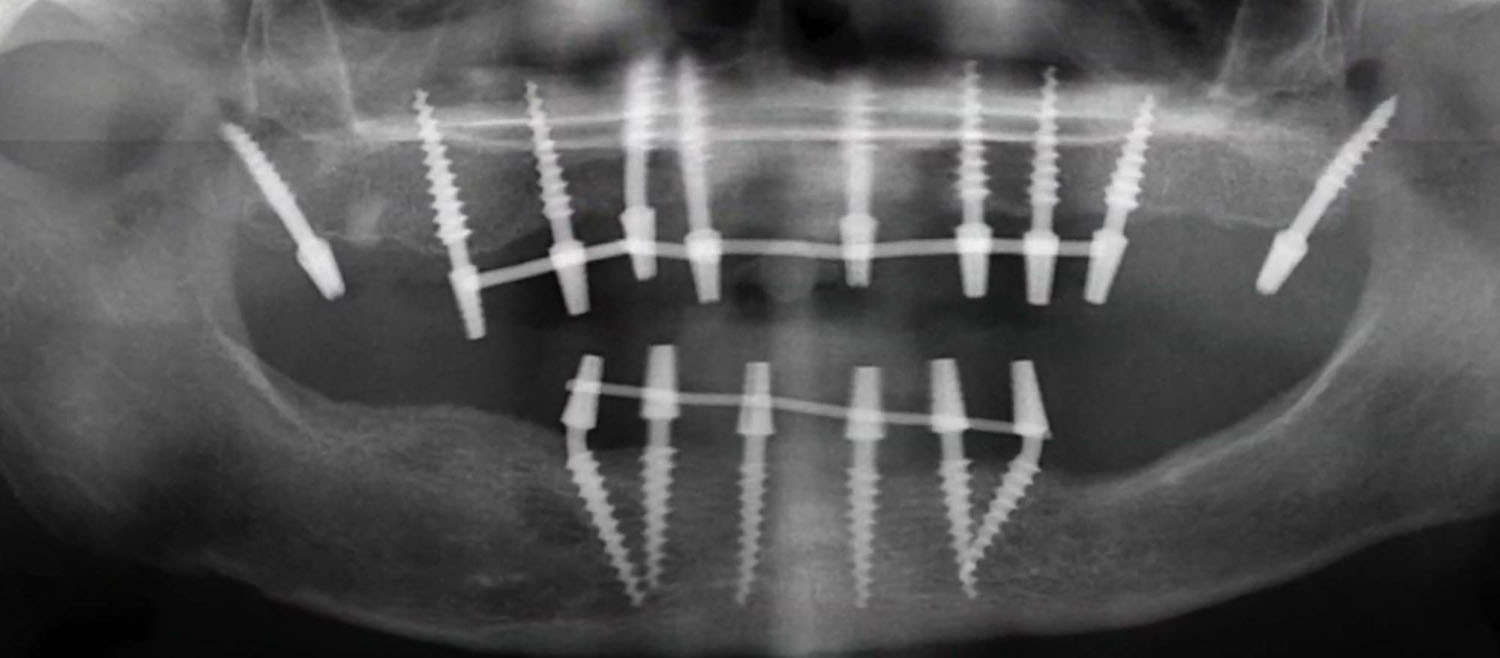

Исследование на рентгене после имплантации зубов

Раздел: Снимки-откровения